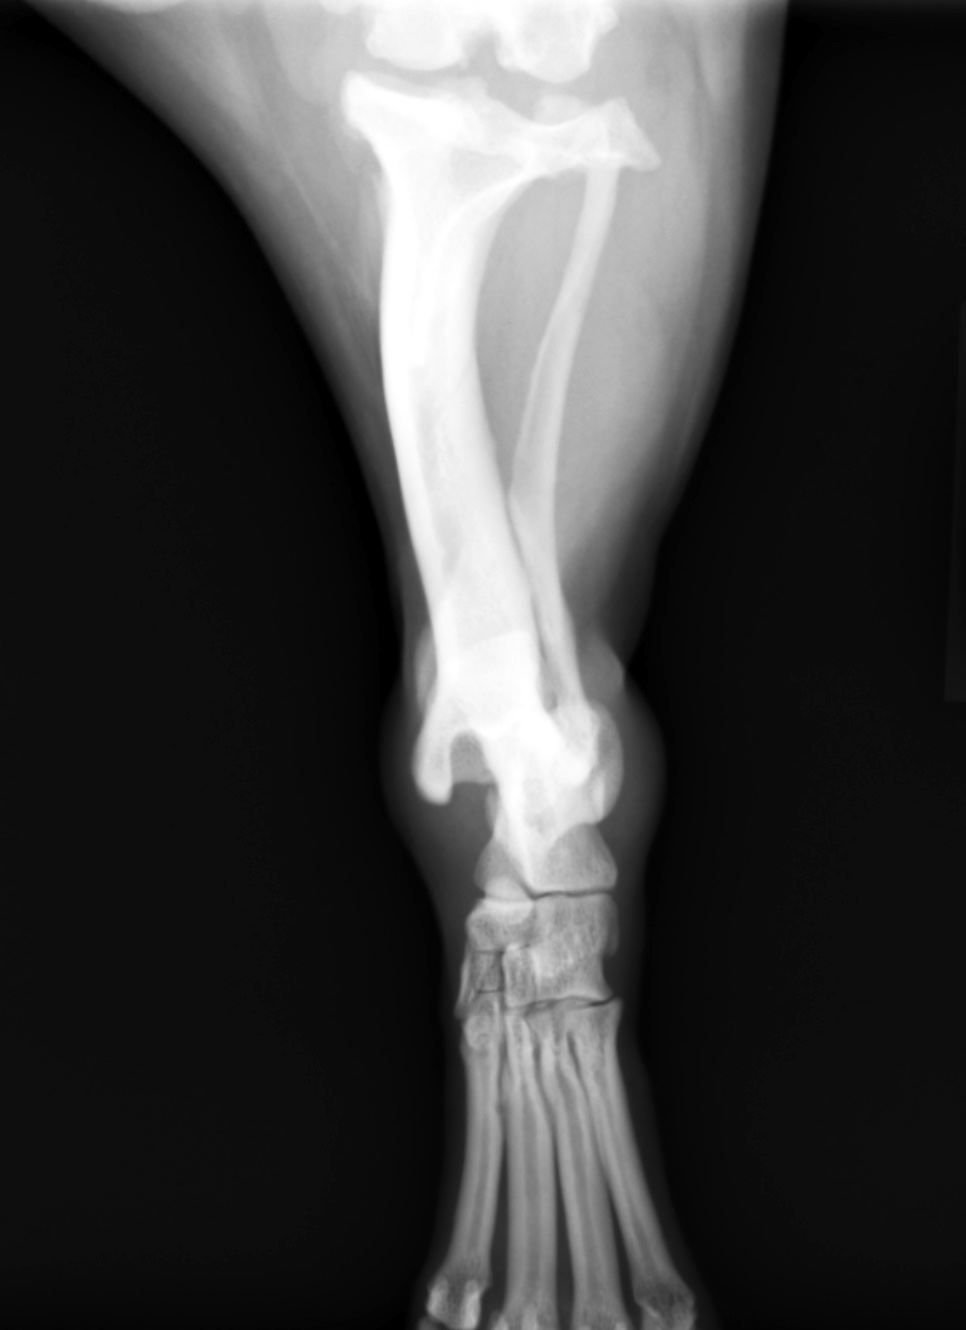

モンテジア骨折 肘の脱臼骨折 脱臼を見逃す 札幌 佐々木勲 クラーク病院